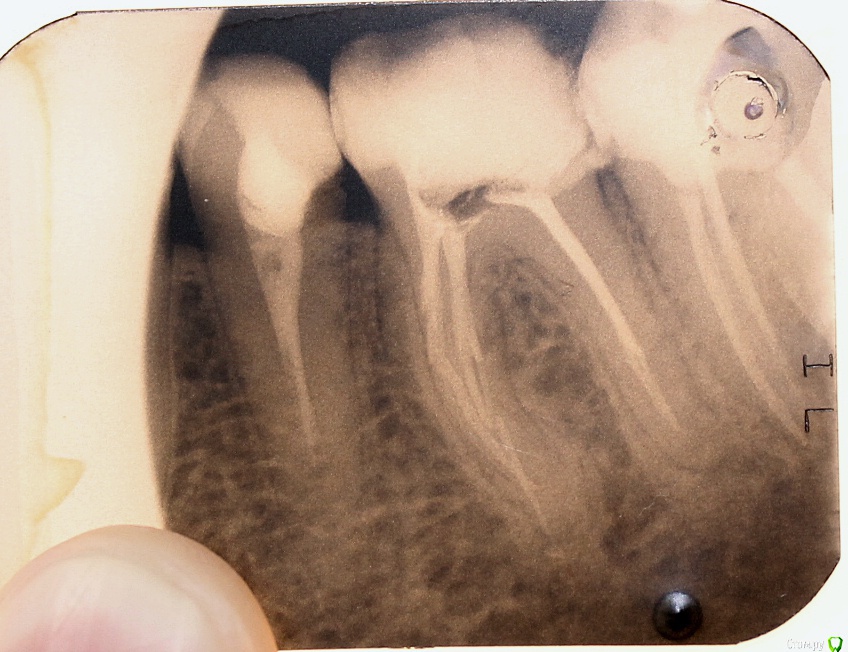

ARislanV Опубликовано 28 мая, 2015 Поделиться Опубликовано 28 мая, 2015 Приветствую всех, Здравствуйте, Начинаем!Пол года назад лечил 36Pt зуб, коронковая часть разрушена на 70 %, восстановил все композитом с перекрытием бугров.Сейчас зуб треснул, по словам удалявшего хирурга трещина до бифуркации. Почему он раскололся? Ведь что интересно, трещина прошла не по краю зуб/пломба ( в самом слабом месте), а посередине пломбы т.е. пломба разорвалась по палам. А какая сила должна была быть, что бы разорвать пломбу по полам?) И следующий вопрос, что делать и как делать, чтобы такого не было? ( потому что мне было очень не приятно видеть такое со своей работой) Ссылка на комментарий

red_butler Опубликовано 28 мая, 2015 Поделиться Опубликовано 28 мая, 2015 Почему он раскололся?Необоснованно расширили показания для реставрации И следующий вопрос, что делать и как делать, чтобы такого не было?протезировать такие зубыP.s. седьмой зуб может повторить судьбу шестого 3 Ссылка на комментарий

M@estro Опубликовано 28 мая, 2015 Поделиться Опубликовано 28 мая, 2015 Этот зуб был разрушен на 70%, конечно его нельзя было восстанавливать пломбой.) Это моя ошибка, из за которой доверие пац ко мне сильно снизилось. Но я не могу понять, при каких случаях надо: - Делать вкладку и коронку- Пломбу и коронку- Вкладку керамическую Объясните пожалуйста?) пломба - 30 процентов разрушения по площади, витальный зуб. Полость мод , отсутие хотя бы двух стенок - вкладка . Депульпированный зуб . если отсутсвует две стенки и площадь разрушения не более 50 % ( первичный пульпит МОЛЯРА ) - вкладка / накладка. С премолярами сложнее , если стенки более 1.5 мм толщиной - можно сделать коронку 3/4 , в остальных случаях - коронка. Если имеем мод полость у моляра, и зуб депульпирован - то это коронка. Ссылка на комментарий

ARislanV Опубликовано 31 мая, 2015 Автор Поделиться Опубликовано 31 мая, 2015 Как я понял, если зуб живой:разрушен до 30% - то пломбаразрушен более 30% - накладка ( керамическая или композитная) депульпированный зуб:разрушен до 50% - накладкаесли более 50% - то вкладки и коронка Так M@estro ? ) 2 Ссылка на комментарий

Чертков Александр Опубликовано 31 мая, 2015 Поделиться Опубликовано 31 мая, 2015 (изменено) Я бы внес небольшую поправку...депульпирован - коронован! 3/4 или полная коронка...ну или винир 360 градусов Изменено 31 мая, 2015 пользователем Чертков Александр 1 Ссылка на комментарий